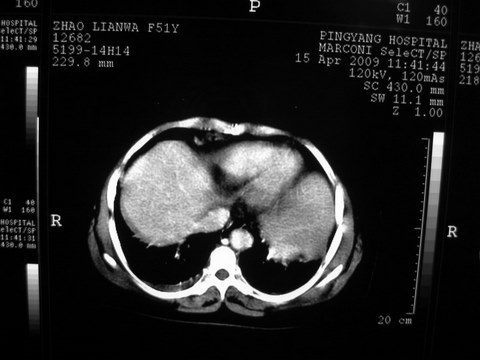

标题: CT19402:肝脏巨大囊实性占位 [打印本页]

标题: CT19402:肝脏巨大囊实性占位

患者 女 51岁 两天前感觉上腹疼,无明显诱因,b超示肝右叶囊实性占位,边缘清楚,其内回声不均匀,ct增强如图,大家看看是什么 ,病人一年前及两月前b超检查只是提示胆囊炎

外院术后,证实肝癌合并出血

特点:1,病灶发展迅速,(2月前正常)[br] 2,囊实性,且并边界清晰光滑,呈右后叶赘生性。囊性区无强化,实性部分较多轻度强化,边界欠清。考虑囊腺癌或囊腺瘤。

出病理 中分化肝细胞癌合并出血